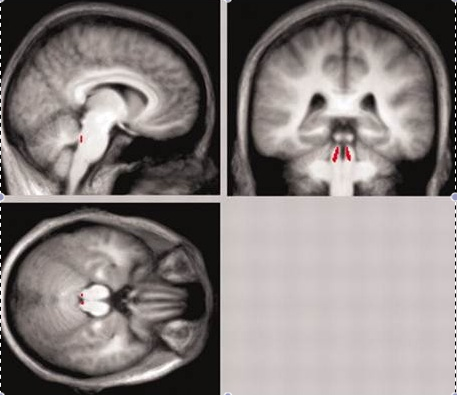

lc1